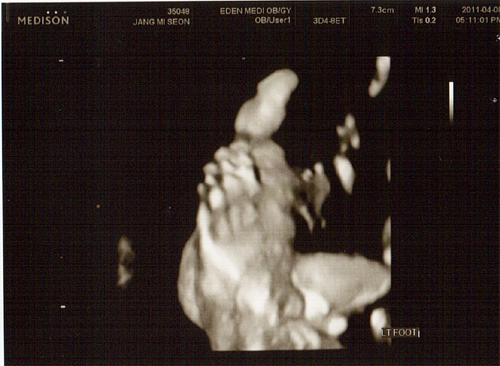

26주 4월 8일(금) 입체 초음파사진